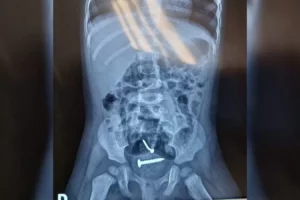

Parafusos no corpo da menina

Elas foram encaminhadas para o hospital e, após a realização dos exames, um raio-X apontou a presença de objetos estranhos dentro do corpo da menina. Ela também tinha lesões nas partes íntimas.

Veja imagem